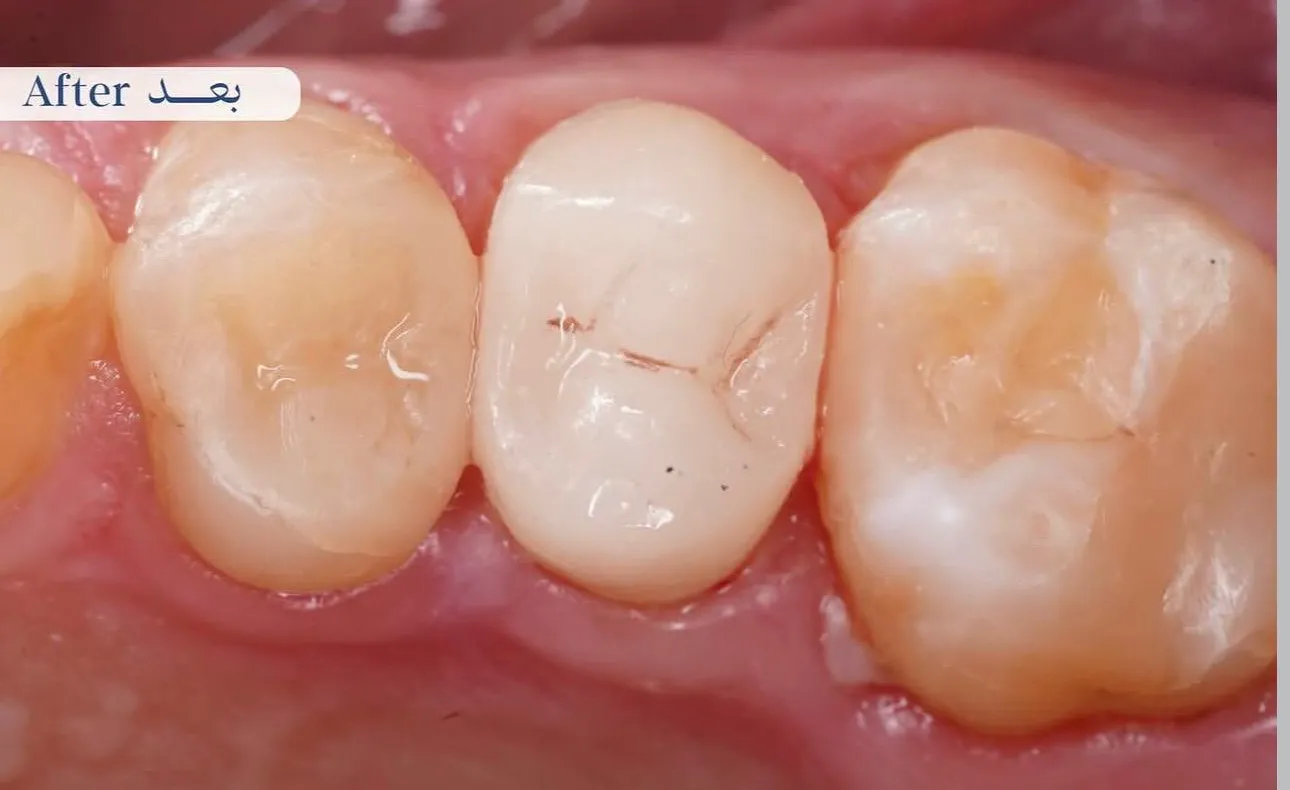

بعد